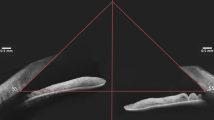

Anterior chamber depth (ACD) was determined from the central inner corneal surface, perpendicular to the corneal surface to the most anteriorly visible part of the IOL (Fig. 3A). The angle were evaluated by using the angle-opening distance at 500 μm (AOD500) and the trabecular-iris angle (TIA), as proposed by Pavlin and associates13. AOD500 was measured on a line perpendicular to the trabecular meshwork at points 500 μm from the scleral spur using calipers of the software in a high-magnification view, and TIA was measured with the apex in the iris recess and the arms of the angle passing through a point on the trabecular meshwork 500 μm from the scleral spur and the point on the iris perpendicularly opposite (Fig. 3B). All four-quadrant values were obtained and averaged for statistical analysis. Any abnormities in the configuration of the anterior segment including the angle, iris, ciliary body, or capsule was described and documented (Fig. 1). The IOL position was also analyzed base on the four-quadrant ultrasound biomicroscopic images (Fig. 2).

(A) UBM images of the anterior chamber and intraocular lens (IOL). Anterior chamber depth (ACD) was determined from the central inner corneal surface, perpendicular to the corneal surface to the most anteriorly visible part of the IOL. (B) Quantitative angle measurement. Angle-opening distance at 500 μm (AOD500) was measured on a line perpendicular to the trabecular meshwork at points 500 μm from the scleral spur. Trabecular-iris angle (TIA) was measured with the apex in the iris recess and the arms of the angle passing through a point on the trabecular meshwork 500 μm from the scleral spur and the point on the iris perpendicularly opposite.